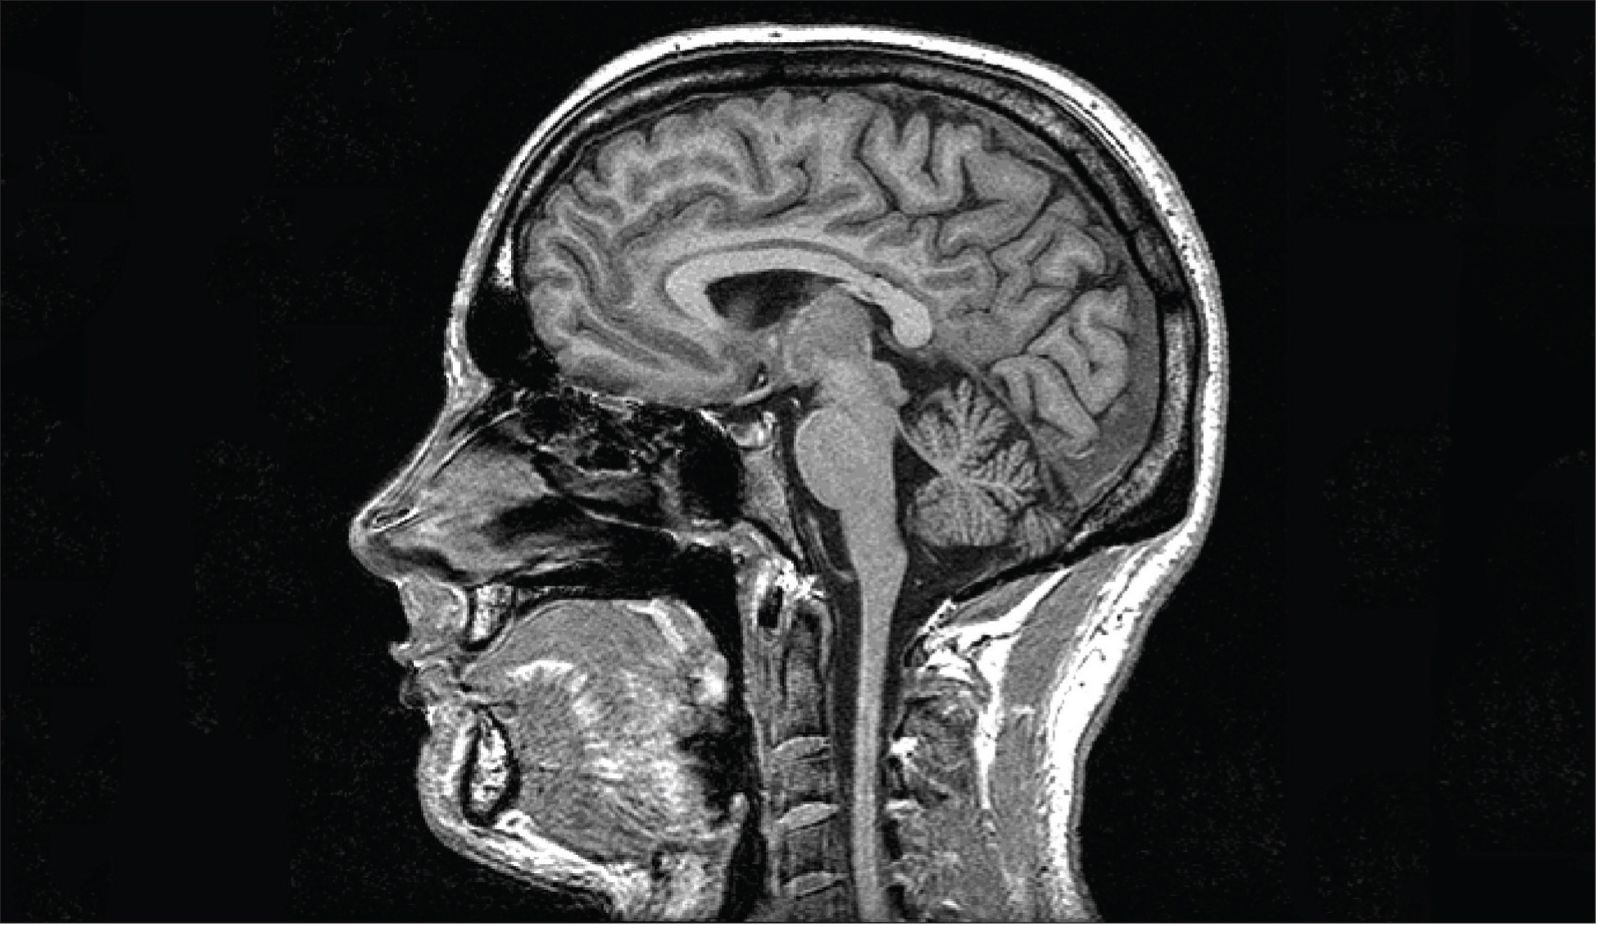

Oxford Centre for Functional MRI of the Brain, Oxford University.

MRI scans can provide detailed images of brain tissue. Here, it displays tissue high in water and fat content in white.

As we gain understanding of the anatomical and functional changes underlying neurological illnesses, it becomes increasingly clear that these changes provide clues for earlier detection — even before symptoms appear. Many disorders, such as Alzheimer’s disease, are accompanied by specific brain activity and structural changes that can be tracked over time using MRI. By comparing this information with a baseline model of a healthy brain, researchers hope to predict which patients might one day develop neurological problems.

As we gain understanding of the anatomical and functional changes underlying neurological illnesses, it becomes increasingly clear that these changes provide clues for earlier detection — even before symptoms appear. Many disorders, such as Alzheimer’s disease, are accompanied by specific brain activity and structural changes that can be tracked over time using MRI. By comparing this information with a baseline model of a healthy brain, researchers hope to predict which patients might one day develop neurological problems.

Although it is still too early for these “markers” to be used as clinical reference points, they could pave the way for objective diagnoses of brain disorders, much as electrocardiograms and laboratory tests are currently used to reveal heart problems. The first step in this process is to produce a generic brain template by averaging the images from hundreds of randomly selected MRI scans. Scientists can then use machine-learning software to characterize the sets of healthy brain scans and the sets of scans known to show disease-associated changes.

Data from predictive neuroimaging can also be useful for guiding personalized treatment options and assessing a treatment’s clinical effectiveness. In studies of major depression, for example, patients whose brain scans showed an overactive amygdala (a brain region involved in emotional processing) were more likely to respond to psychotherapy. However, patients who exhibited higher activity in the anterior insula (another brain region involved in emotions) tended to improve with medication, but not with psychotherapy. In the future, psychiatrists could offer patients the best possible course of treatment based on their own biological characteristics, rather than relying only on symptoms or treatment preferences.